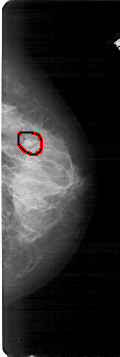

FILE: A_1682_1.RIGHT_MLO.OVERLAY

TOTAL_ABNORMALITIES 1

ABNORMALITY 1

LESION_TYPE MASS SHAPE OVAL MARGINS OBSCURED

ASSESSMENT 4

SUBTLETY 3

PATHOLOGY BENIGN

TOTAL_OUTLINES 1

BOUNDARY